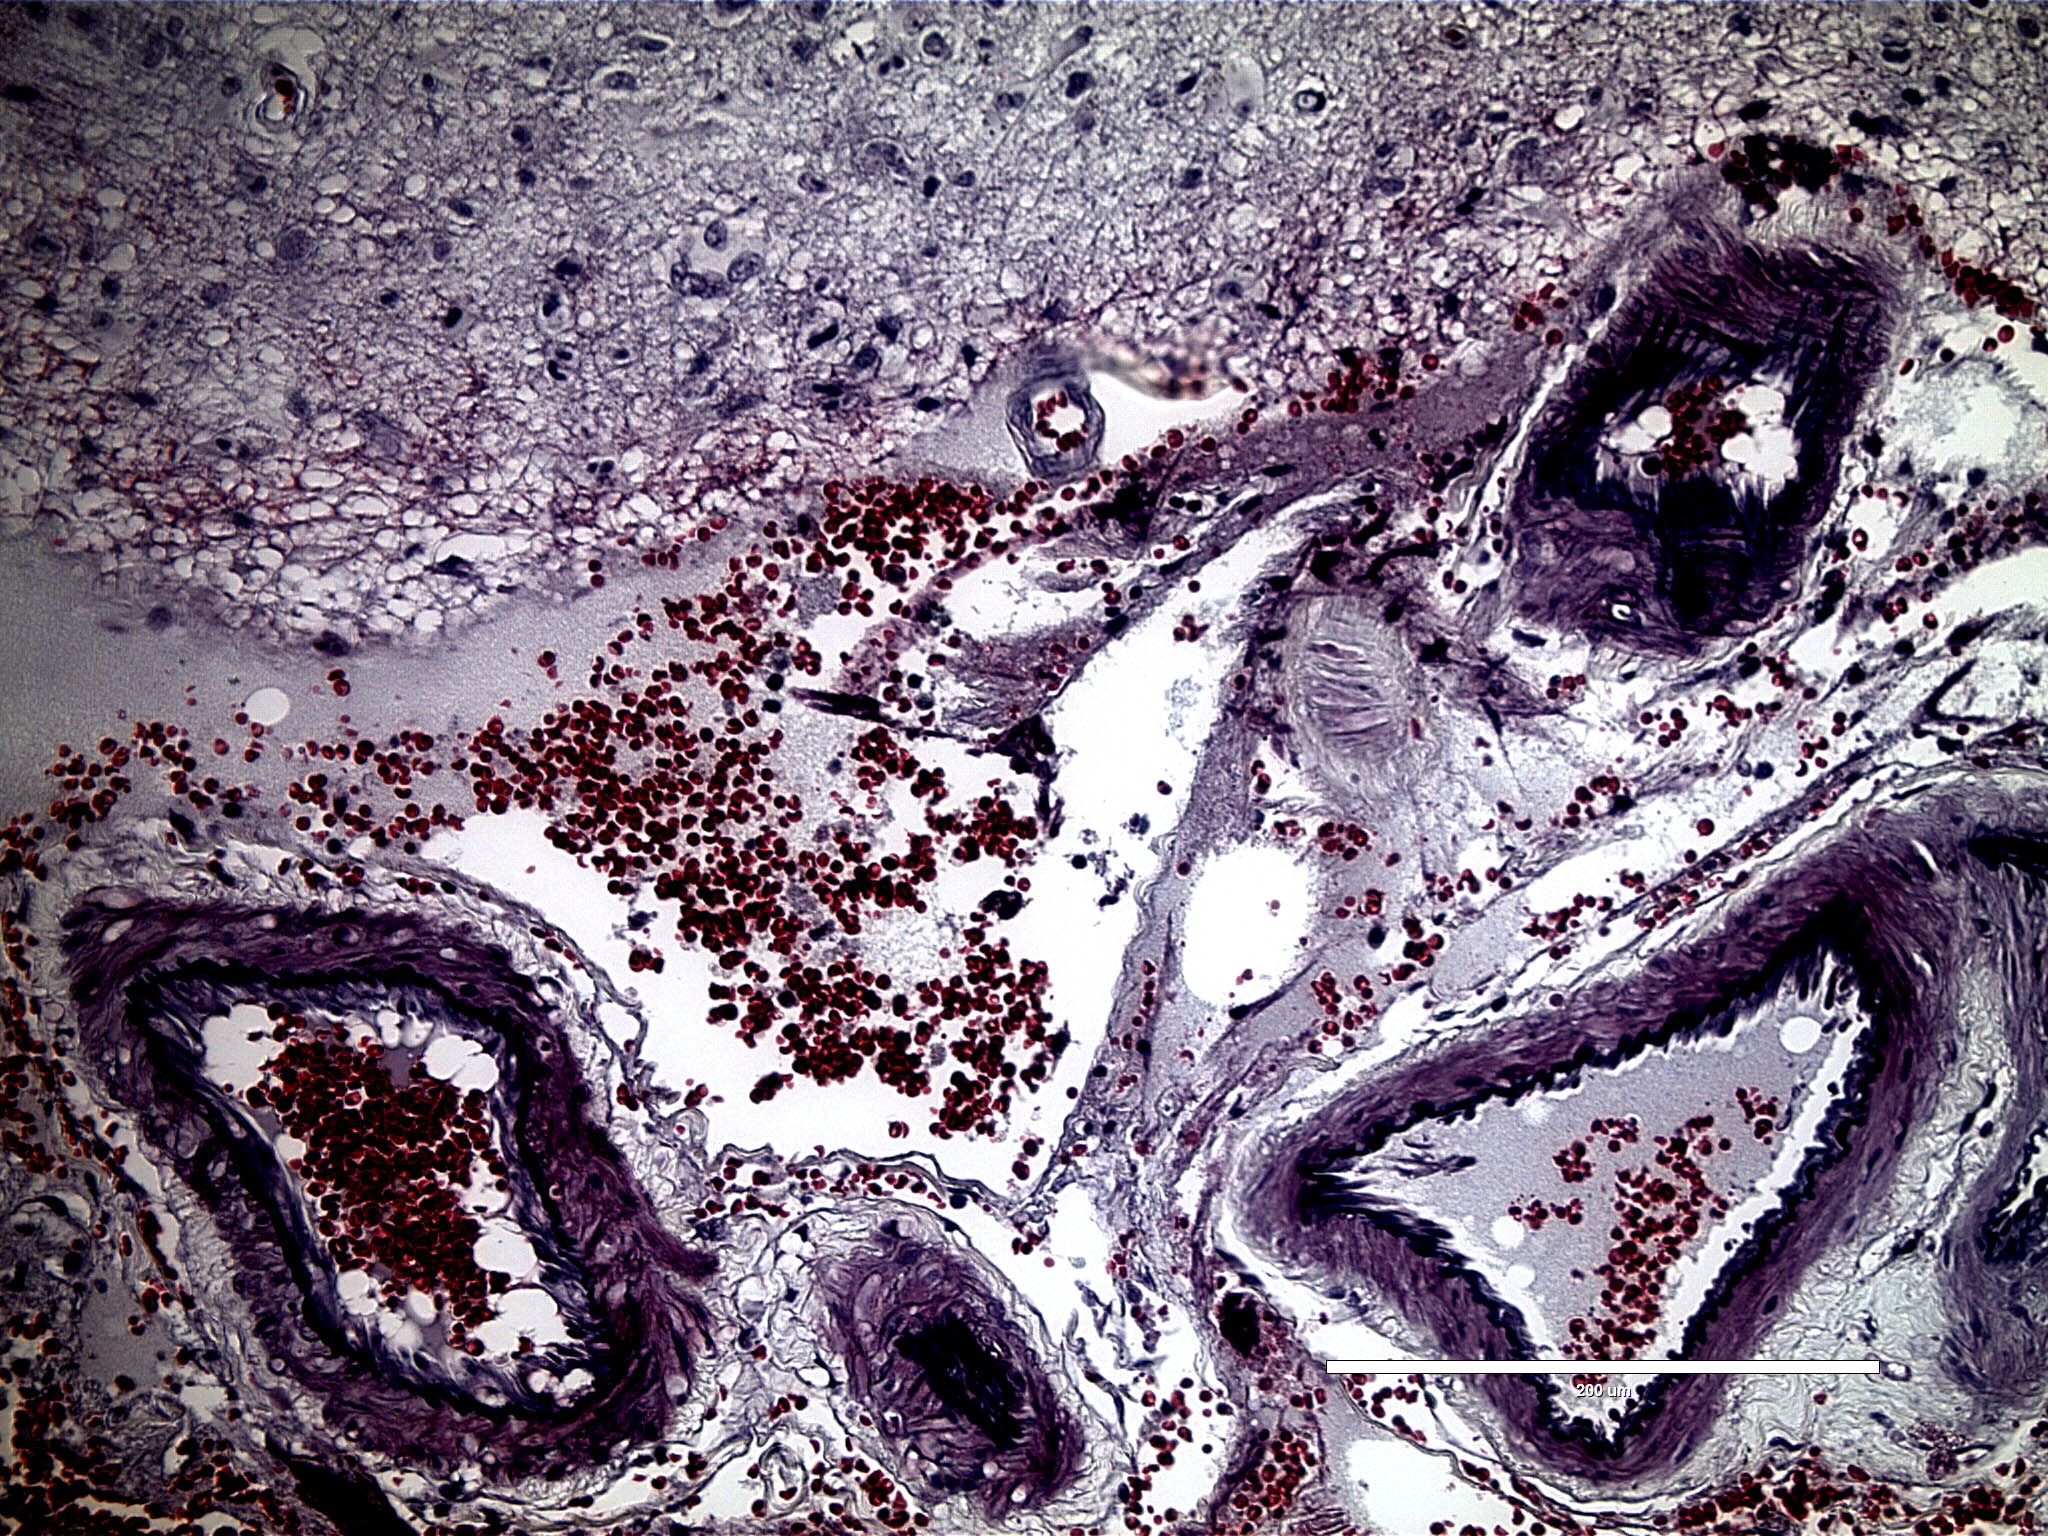

Munson Lab Vt . The munson lab studies the tumor microenvironment in cancers, including glioblastoma, the deadliest form of brain cancer. Our research program aims to understand and harness the tumor microenvironment to study and treat triple negative breast cancer and. Jenny munson is a principal investigator at the fralin biomedical research institute who studies the tumor. Our research focuses on the. Led by principal investigator jenny munson, ph.d., director of the fralin biomedical research institute cancer reearch group, the munson. Jennifer munson, associate professor at the fralin biomedical research institute at vtc, shared her data on fluid flow in brain tumors with virginia. In 2019, he started his postdoctoral research at ucsf in dr. Engineering cancer to cure it. Jennifer munson, associate professor at the fralin biomedical research institute at vtc, shared her data on fluid flow in. Our mission is to investigate and evaluate the tumor microenvironment, the tissue around a tumor that is involved in invasion and metastasis.